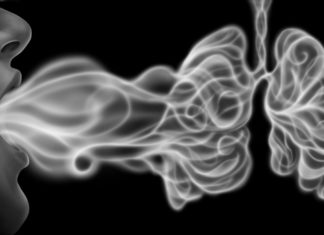

An article on the Radiology Business website discusses a study regarding the health of the lungs and using fMRI Lung scans to assess the effects of smoking and vaping.

Functional lung tests and Un-enhanced Lung fMRI’s (functional Magnetic Resonance Imaging) were performed to establish baseline results and to observe changes after the participants vaped or smoked.

Evaluating the imaging showed that current and past smokers showed signs of significant localised decrease in lung perfusion after smoking, compared to the baseline results.

Lung Perfusion records the blood supply through the lungs. A lower Lung Perfusion result means there is less blood circulating and could be as a result of damage, clots or disease.

However the nicotine vapers results showed that lung perfusion actually increased after vaping.